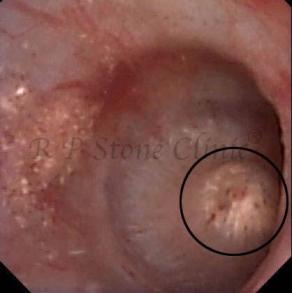

Kidney stone is a solid mass of CRYSTALS. It is the process of crystallization which initiates the formation of kidney stones. This happens in nephrons or units of kidney. Once a small crystal is formed, it can both grow & unite with other crystals leading to the formation of small concretion which eventually forms a stone. Once these large crystals detach from the collecting ducts, the process of stone formation starts in the renal collecting system. A recurrent kidney stone former is advised to know a little bit about something known as Randall’s plaque. Alexander Randall discovered plaques on the renal papillae eight decades back based on examination of 1154 pairs of autopsied Kidneys. He described these renal papillary lesions as cream colored or milk patch areas composed of calcium phosphate & calcium carbonate. These plaques could act as NIDUS for formation of KIDNEY STONE. Calcium Oxalate stone can form on this nidus & then detaches from this plaque to become a free floating stone in the collecting system of kidney

These images are taken as snap shots from the video recording of RIRS Surgery done at our hospital. These are Randall’s Plaques seen with Digital FLEX XC & Digital FLEX XC S. The cream or whitish patches are seen on the tips of RENAL PAPILLAE as seen in images below.

Randall’s Plaques may lead to the formation of Stones.

Those kidney stone patients who have Randall’s Plaques in their kidneys are more likely to form stones again (Recurrent Stones).

Stone Patients in whom Randall’s Plaques are detected at the time of RIRS Surgery should undergo regular ultrasound examination for early detection of stones.

Patients of Stones with Randall’s Plaques in their Kidneys should drink plenty of fluids in addition to Orange Juice & Lemonade.